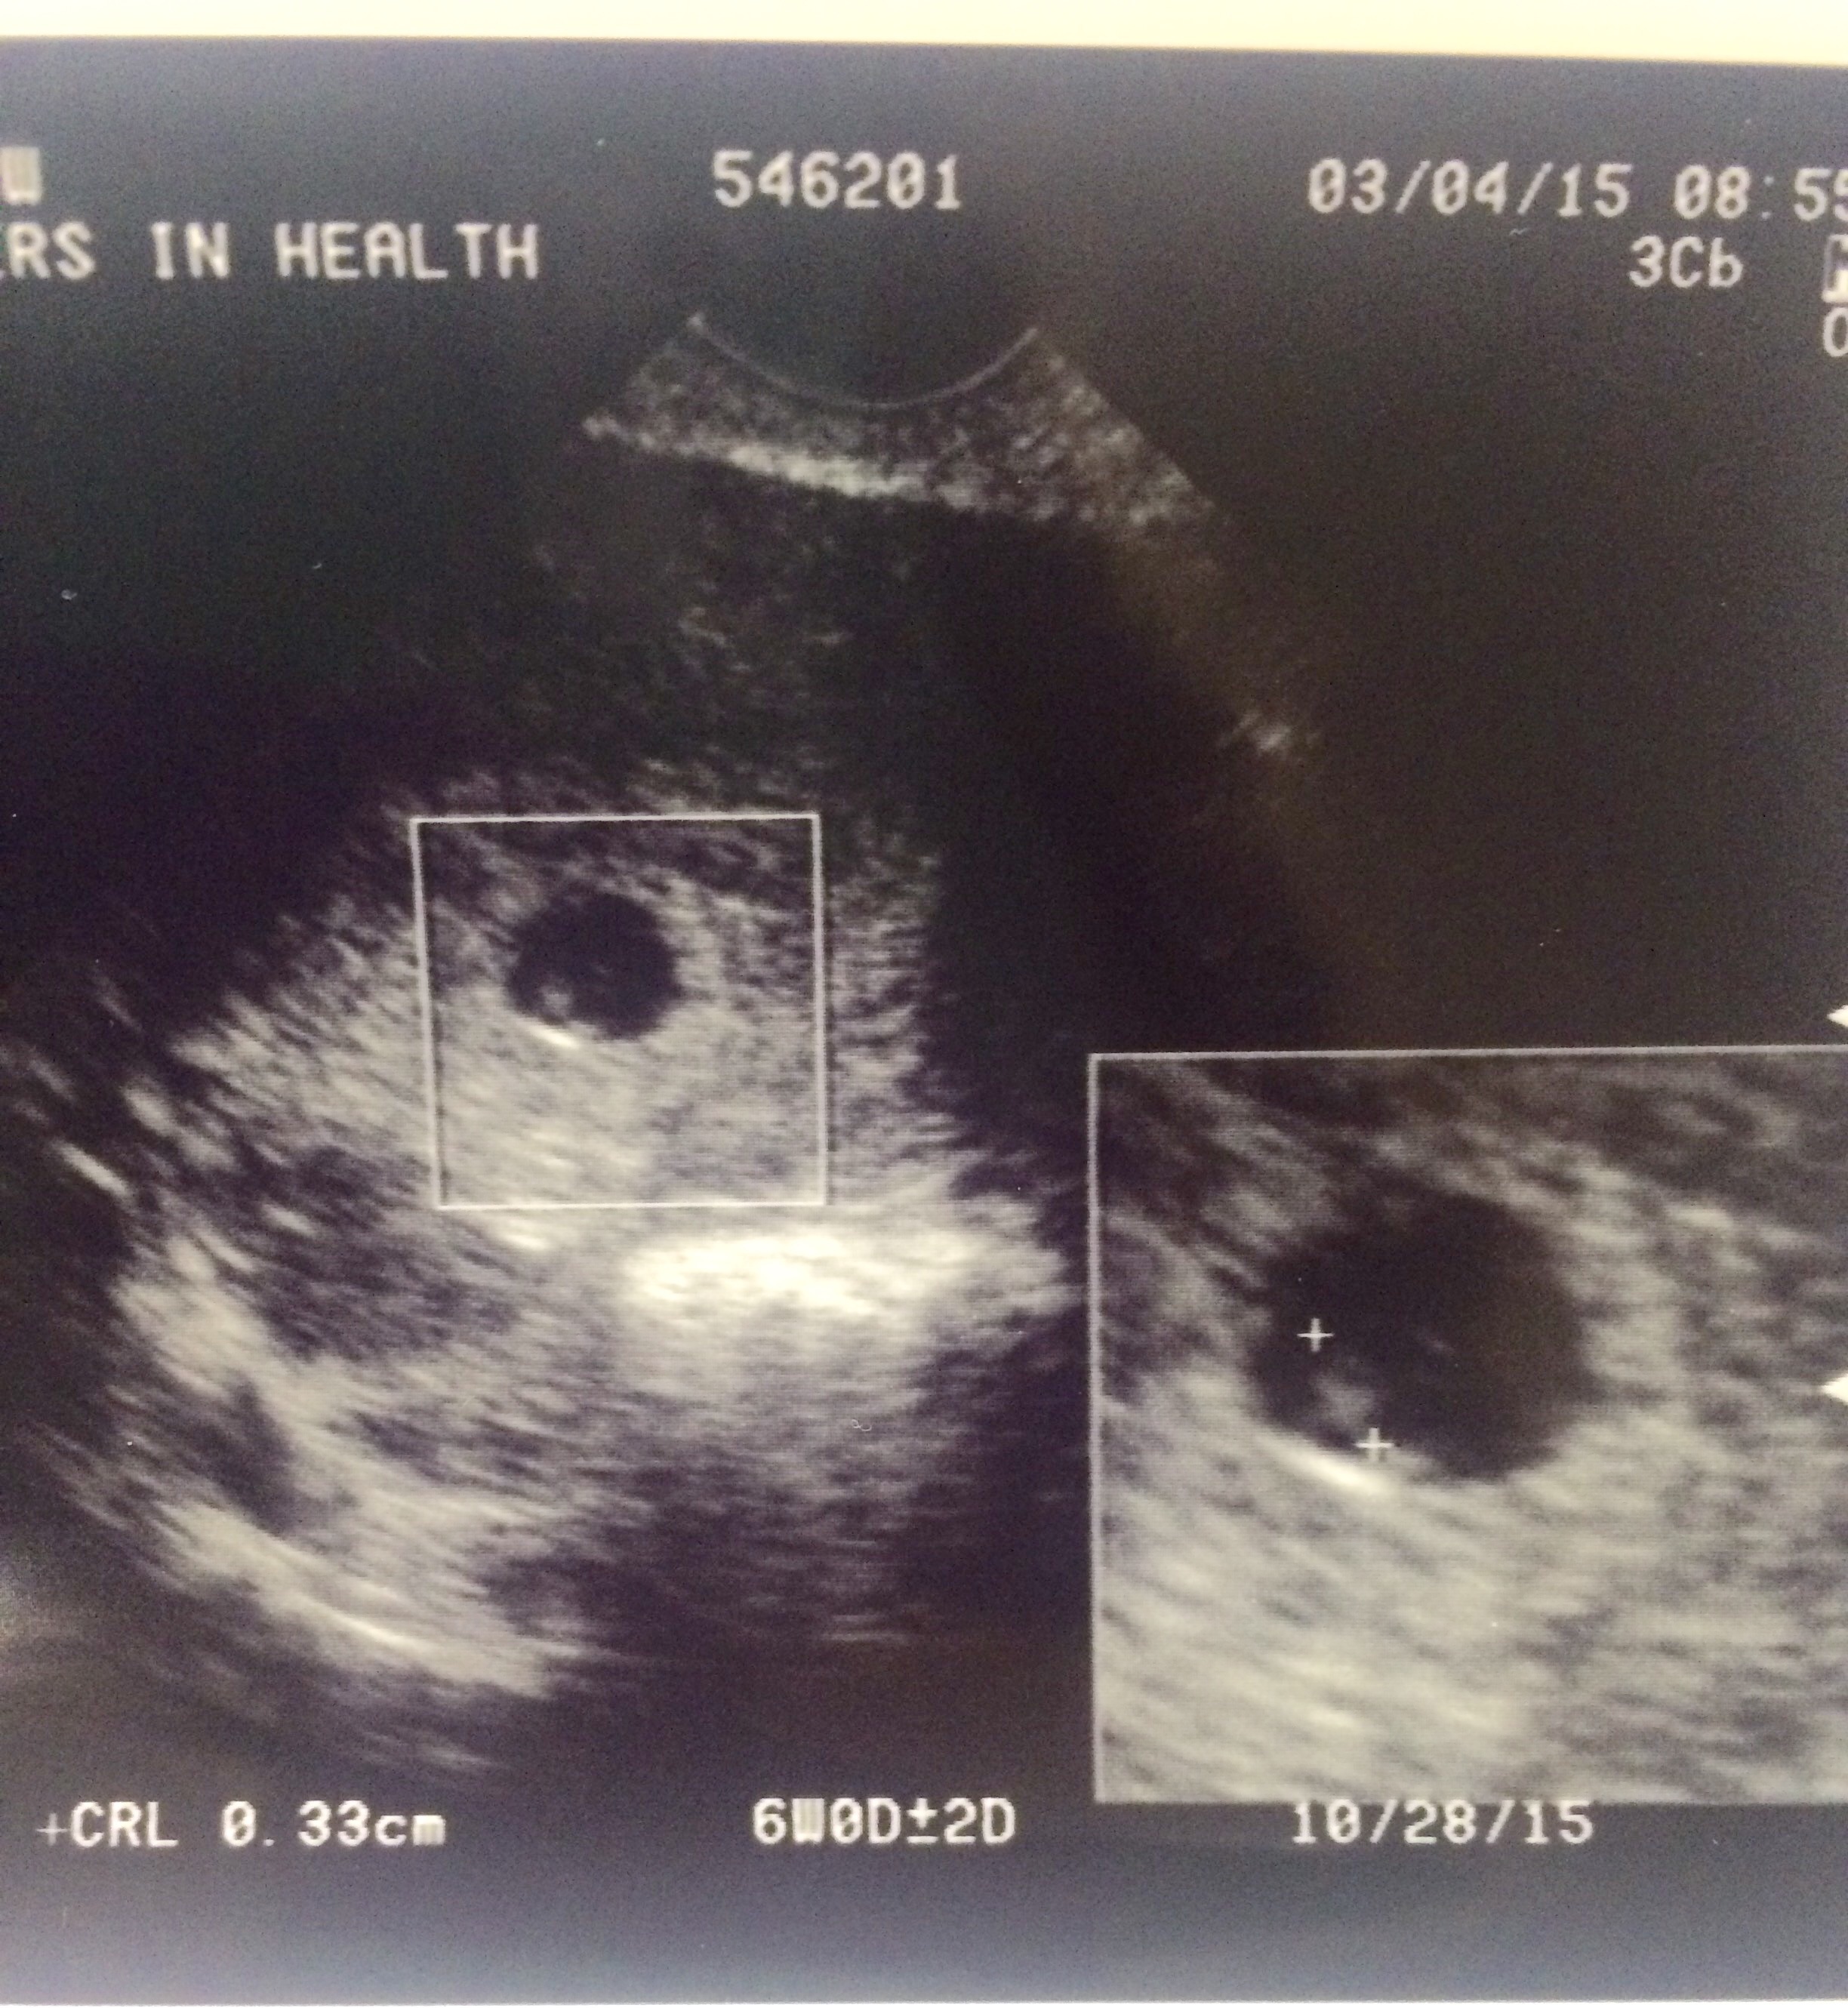

• First ultrasound this morning, measuring 6 weeks 4 days heartbeat of 123 most amazing thing ever!